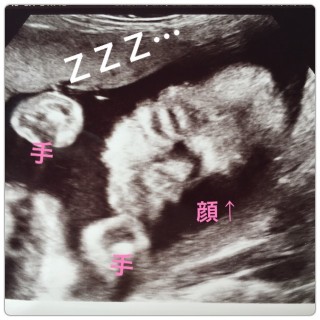

男の子です!写真では手で顔を隠しててわからないけど、動画だと私似かな!?と(*^^*)800gくらいになったみたいで、どんどん大きくなってて嬉しいです♪